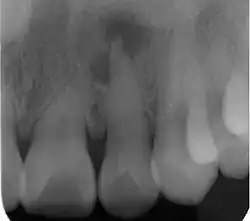

| Radiograph (X-ray) showing microdontia. Note also periapical lesion on the maxillary left lateral incisor. | |

Microdontia is a condition in which one or more teeth appear smaller than normal. In the generalized form, all teeth are involved. In the localized form, only a few teeth are involved. The most common teeth affected are the upper lateral incisors and third molars.

Teeth affected by microdontia may also have abnormal shape, and the abnormal size may affect the whole tooth, or only a part of the tooth.[1]